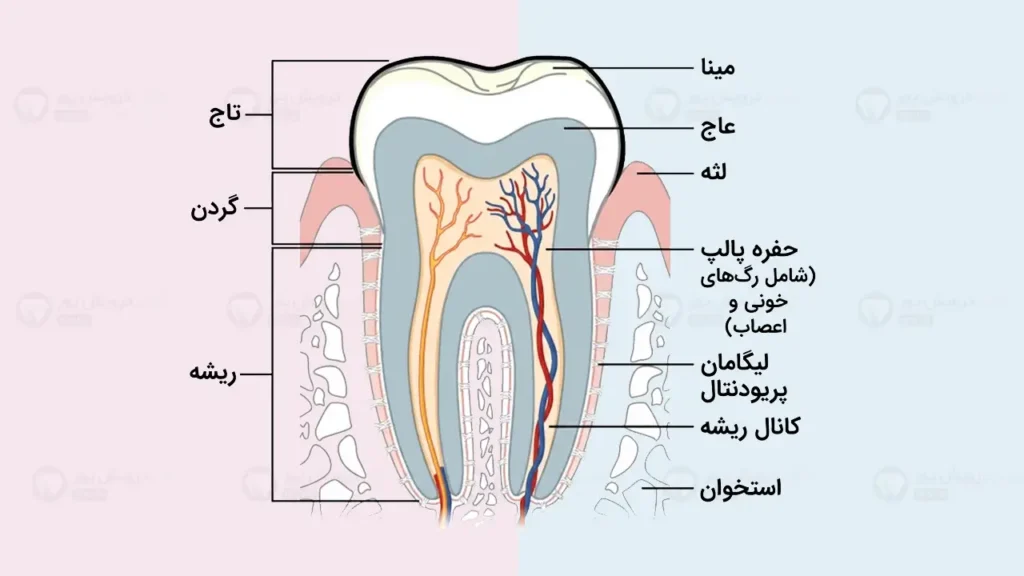

برای اینکه بفهمید چرا یک سیم ثابت پس از درمان ارتودنسی تان باید پشت دندان ها باشد (یا ریتینر متحرک)، اول باید طبیعت دندان ها را بشناسید. ببینید دندان های ما مثل سربازهای مطیع نیستند که وقتی آن ها را به خط کردیم، همان جا بی حرکت بمانند. دندان ها توسط الیافی کشسان به لثه و استخوان وصل هستند. این الیاف مثل کِش عمل می کنند.

وقتی ما دندان را با ارتودنسی حرکت می دهیم، این الیاف یا رباط ها کشیده می شوند. به محض اینکه وسایل را برمیداریم (پس از پایان درمان)، این الیاف دوست دارند جمع شوند و دندان را به همان جای کج و کوله اولیه اش برگردانند. ما به این پدیده می گوییم “حافظه دندانی”.

علاوه بر این، استخوانی که تازه دور ریشه دندان شکل گرفته، هنوز نرم است و ماه ها زمان می خواهد تا سفت شود. مدت زمان استفاده از ریتینر ثابت دقیقاً زمانی است که ما با این نیروهای طبیعی می جنگیم تا دندان ها در جای جدیدشان تثبیت شوند.